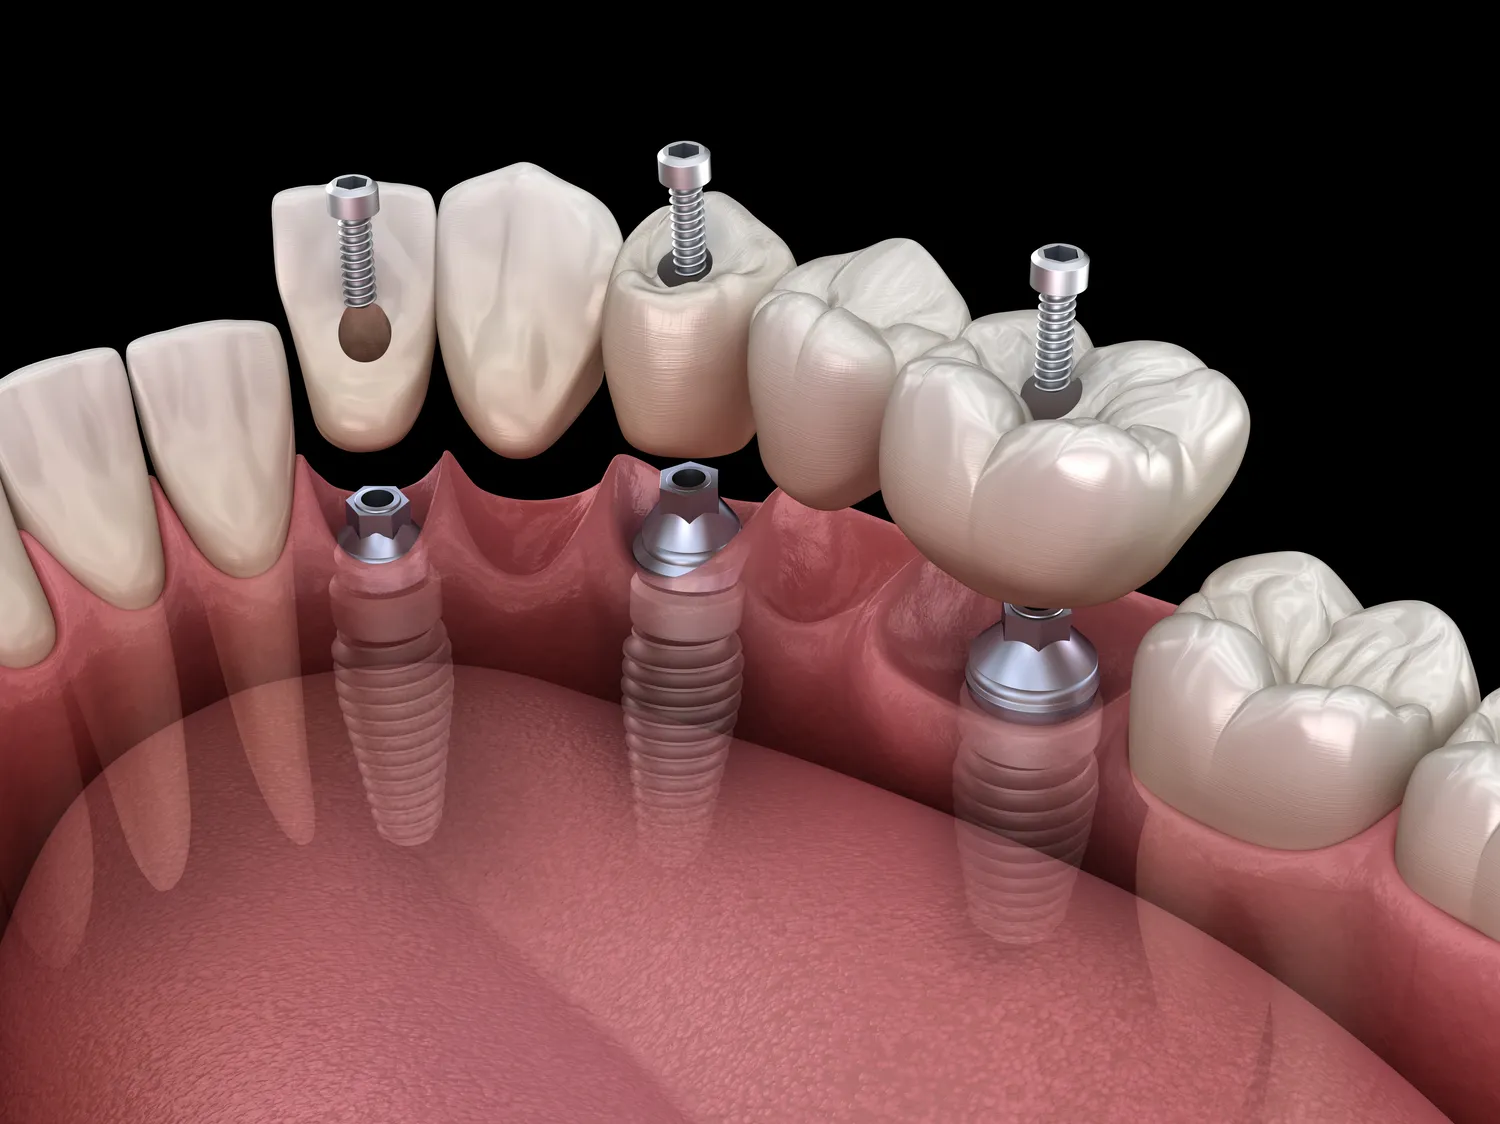

Oprócz wspomnianych zabiegów, stomatolog ogólny często zajmuje się również prostymi ekstrakcjami zębów, leczeniem urazów zębów czy protetyką stomatologiczną, na przykład wykonując wkłady koronowo-korzeniowe, mosty czy protezy ruchome. W przypadkach wymagających bardziej specjalistycznej interwencji, dentysta ogólny kieruje pacjenta do odpowiedniego specjalisty. Warto podkreślić, że współpraca między stomatologiem ogólnym a innymi specjalistami jest kluczowa dla zapewnienia pacjentowi najlepszej możliwej opieki. Niezależnie od tego, czy potrzebujesz rutynowej kontroli, leczenia bólu zęba, czy prostego zabiegu estetycznego, stomatolog ogólny jest osobą, do której powinieneś się zwrócić w pierwszej kolejności.

W przypadku poważniejszych problemów z zębami lub kośćmi szczęki, które wymagają interwencji chirurgicznej, stomatolog może skierować pacjenta do chirurga stomatologicznego. Dotyczy to między innymi skomplikowanych ekstrakcji zębów (na przykład zębów mądrości, które są zatrzymane), resekcji wierzchołka korzenia, leczenia przetok, czy też przygotowania jamy ustnej do zabiegów implantologicznych. Chirurgia stomatologiczna obejmuje również procedury związane z leczeniem nowotworów jamy ustnej i szczęki.

- Protetyk stomatologiczny: W przypadku konieczności wykonania skomplikowanych uzupełnień protetycznych, takich jak rozbudowane mosty, korony na implantach, czy skomplikowane protezy ruchome.

- Implantolog: Specjalista od chirurgicznego wszczepiania implantów zębowych, które stanowią podstawę dla koron, mostów lub protez.